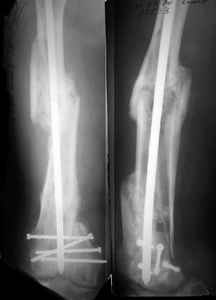

I presented a series of ~25 such cases at EuroTrauma'2004. Many cases were discussed here. I attach am example. Look also recent cases at http://www.hwbf.org/hwb/conf/alex58/scfx.htm,

http://www.hwbf.org/hwb/conf/alex63/alex63.htm

At that moment we had in stock only the 10 mm solid nails so of course there was no idea about early weight bearing. But it was quite enough for early knee ROM excersises (see attached). Two locking screws through the distal block provided that.